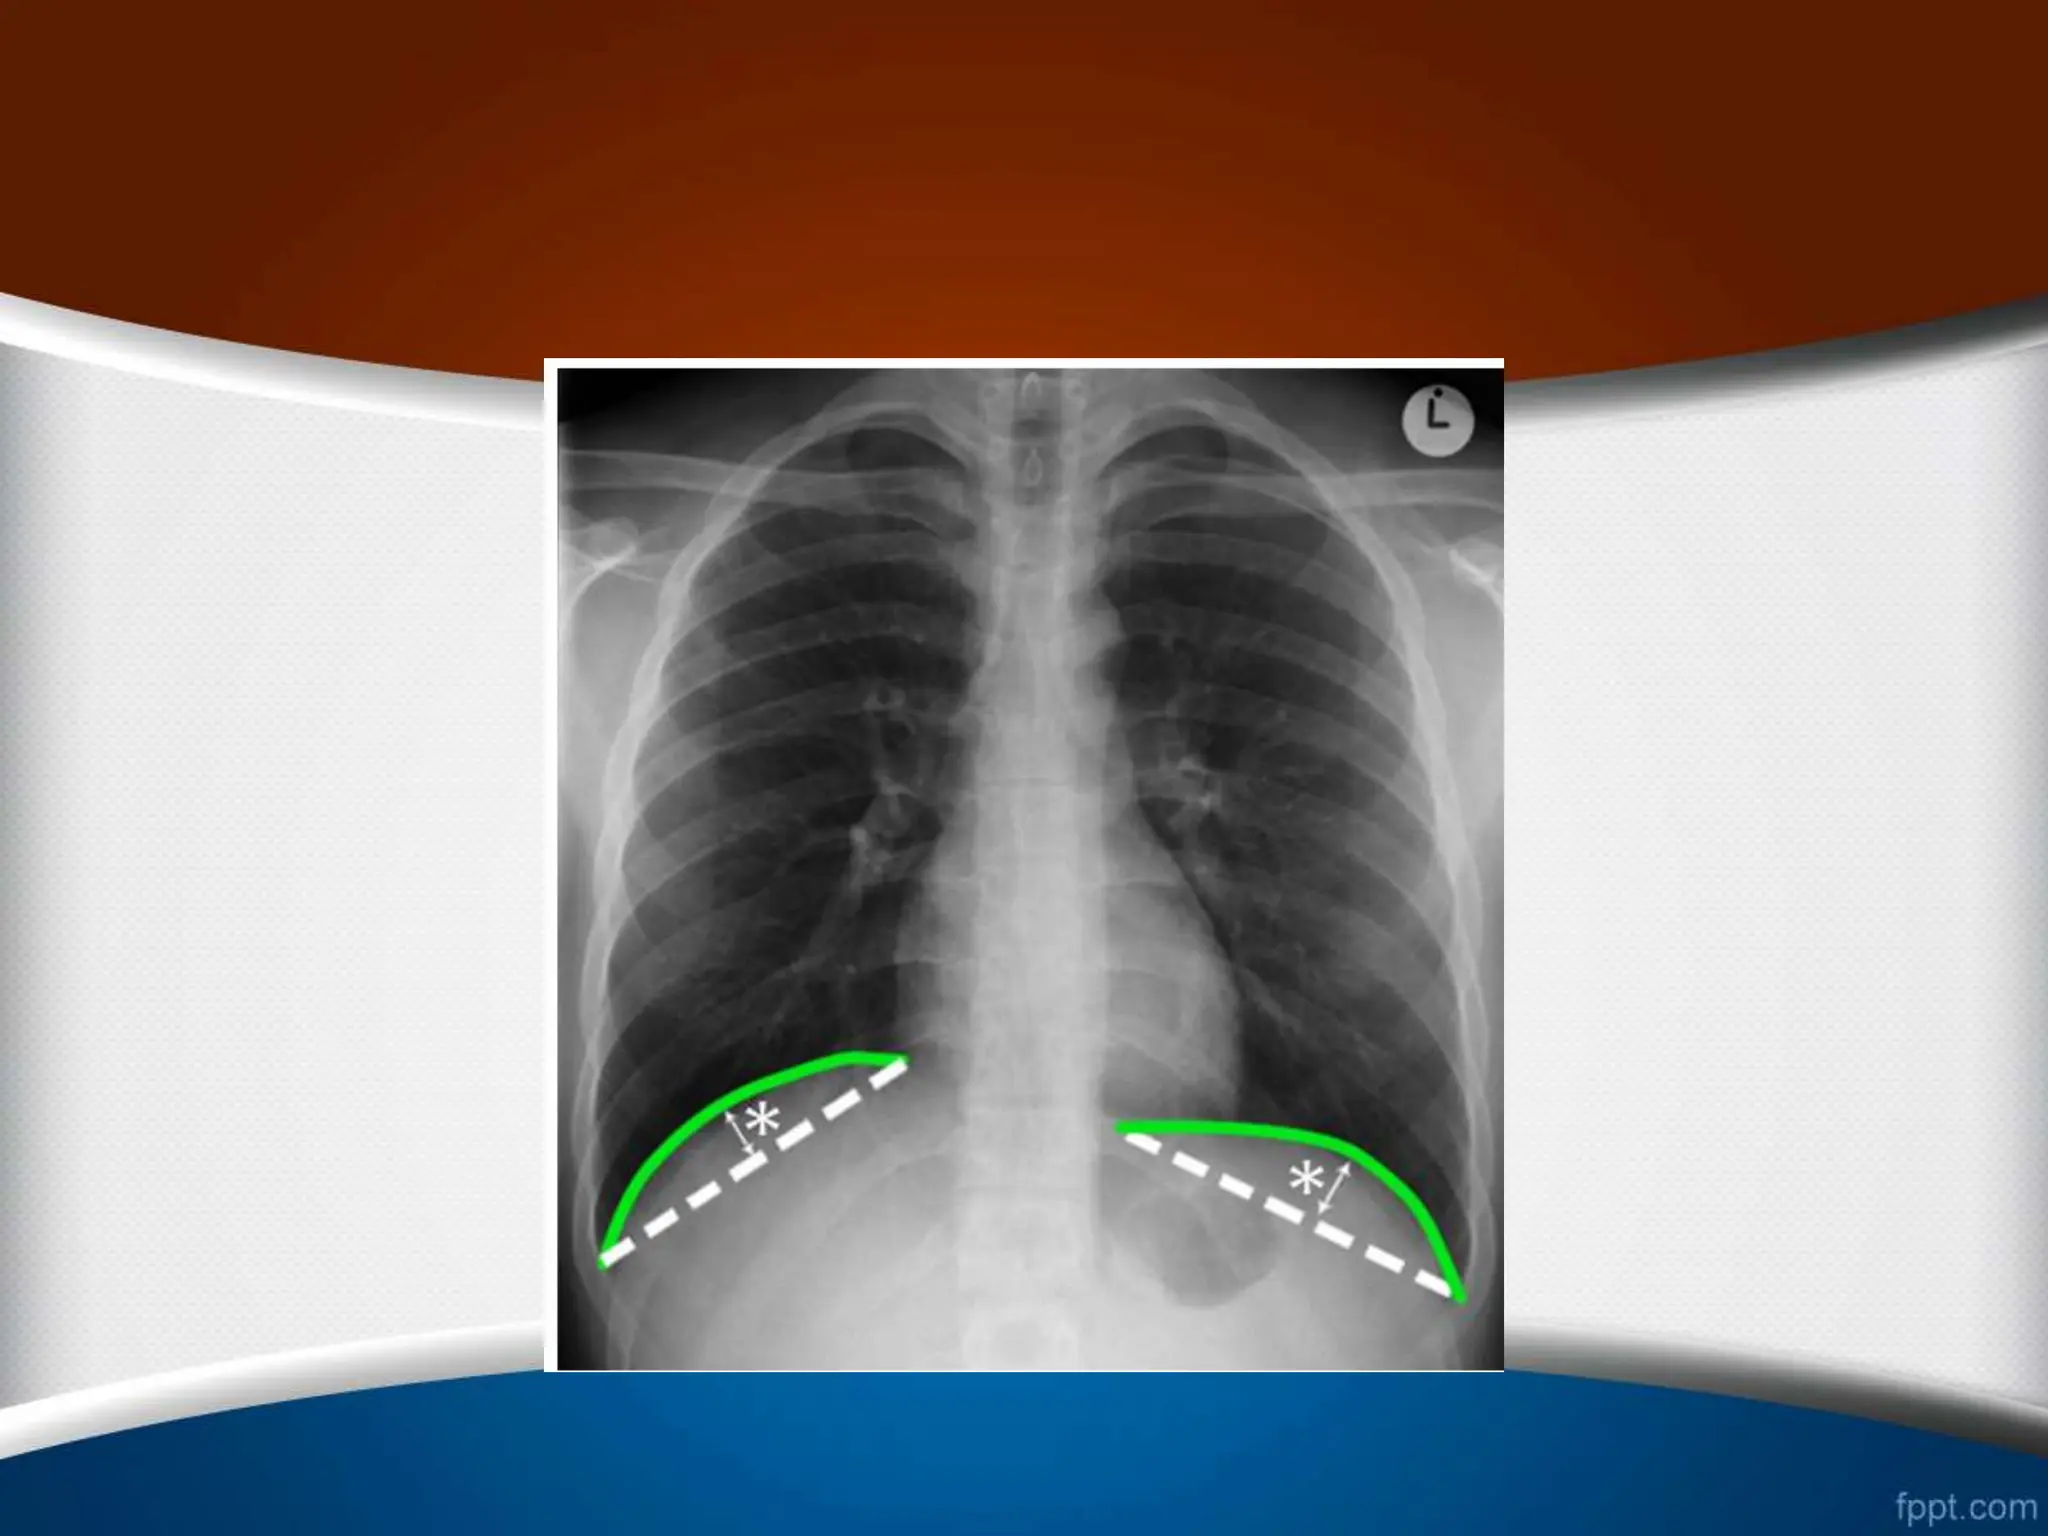

‫دم‬ ‫میزان‬

•

1

-

‫مشاهده‬

9

‫تا‬

12

‫یا‬ ‫خلفی‬ ‫دنده‬

6

‫در‬ ‫قدامی‬ ‫دنده‬

CXR

‫فرونتال‬

PA

‫میدکالویکول‬ ‫خط‬ ‫در‬

2

‫زاویه‬ ‫از‬ ‫اگر‬

‫خط‬ ‫کاردیوفرنیک‬ ‫به‬ ‫کوستوفرنیک‬ ‫ی‬

‫ی‬

‫فاص‬ ‫باشد‬ ‫شده‬ ‫انجام‬ ‫عمیق‬ ‫دم‬ ‫که‬ ‫صورتی‬ ‫در‬ ‫بکشیم‬

‫بین‬ ‫له‬

‫از‬ ‫بیشتر‬ ‫باید‬ ‫دیافراگم‬ ‫و‬ ‫خط‬ ‫این‬

1.5

‫سانتی‬

‫باشد‬ ‫متر‬

.

3

‫باشد‬ ‫شده‬ ‫پوشیده‬ ‫دیافراگم‬ ‫توسط‬ ‫قلب‬ ‫کناره‬